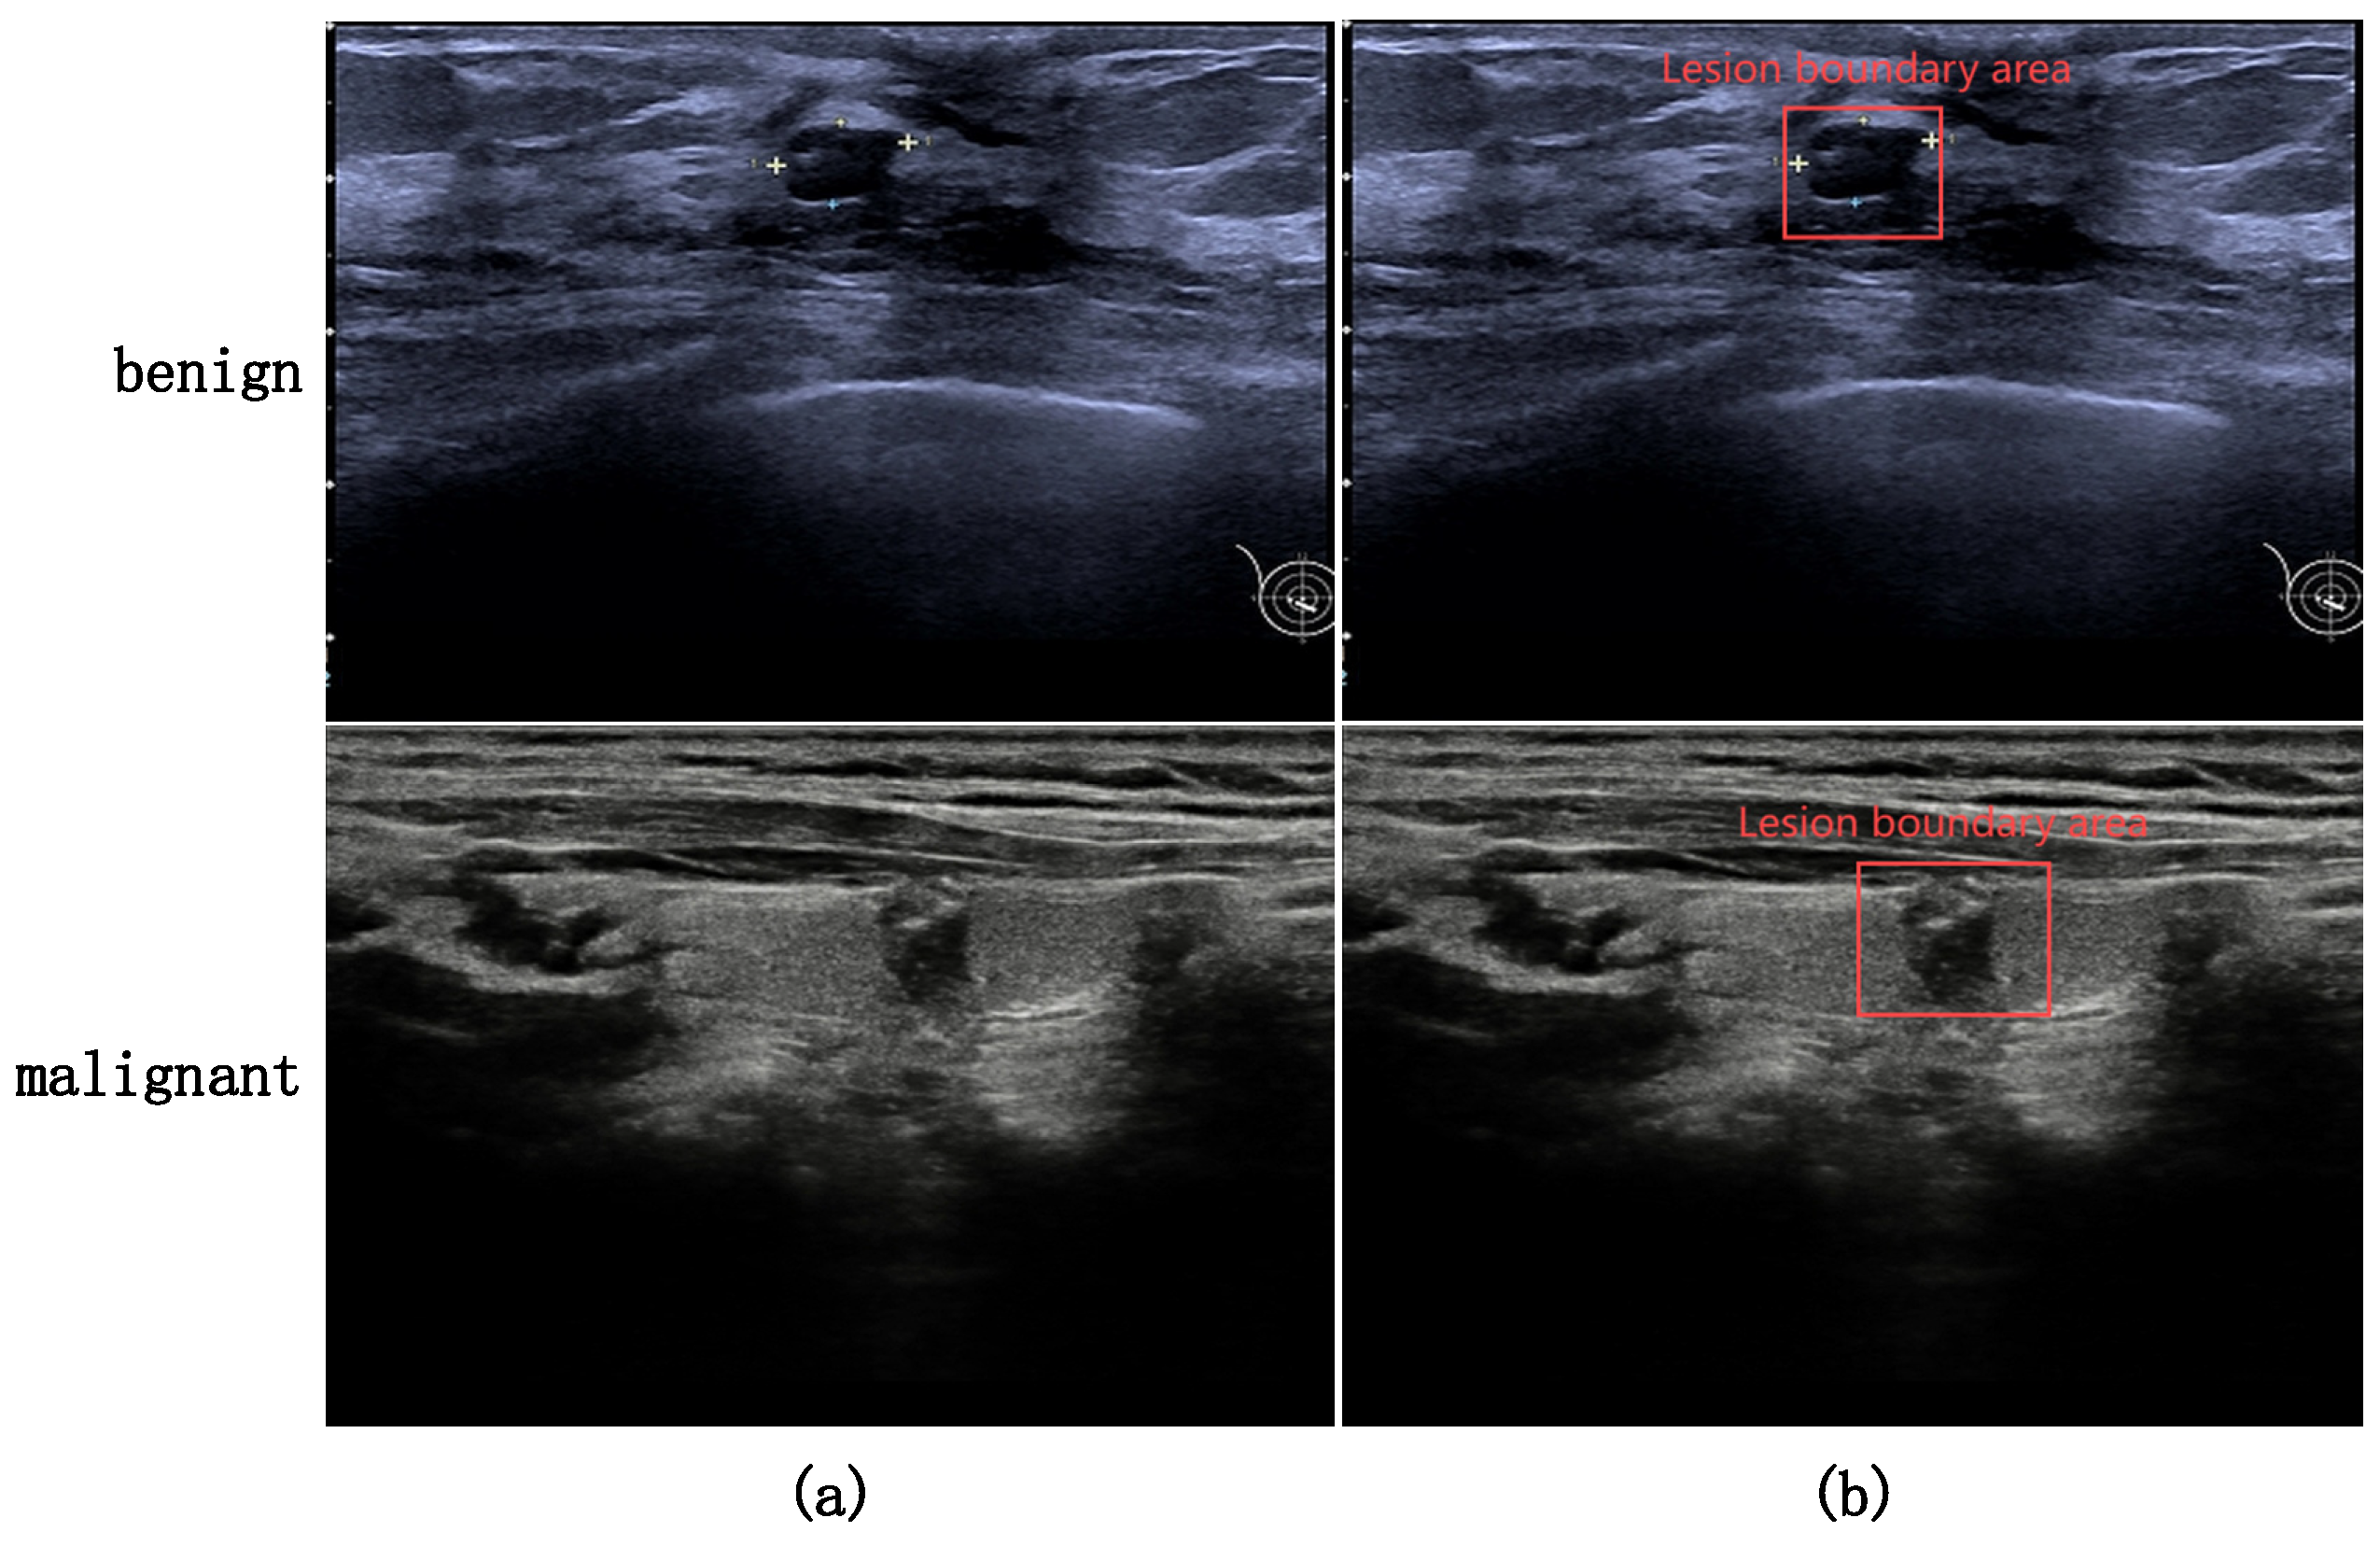

4.1. Dataset

- Yang, X.; Geng, H.; Wang, X.; Li, L.; An, X.; Cong, Z. Identification of lesion location and discrimination between benign and malignant findings in thyroid ultrasound imaging. Sci. Rep. 2024, 14, 32118. [Google Scholar] [CrossRef] [PubMed]